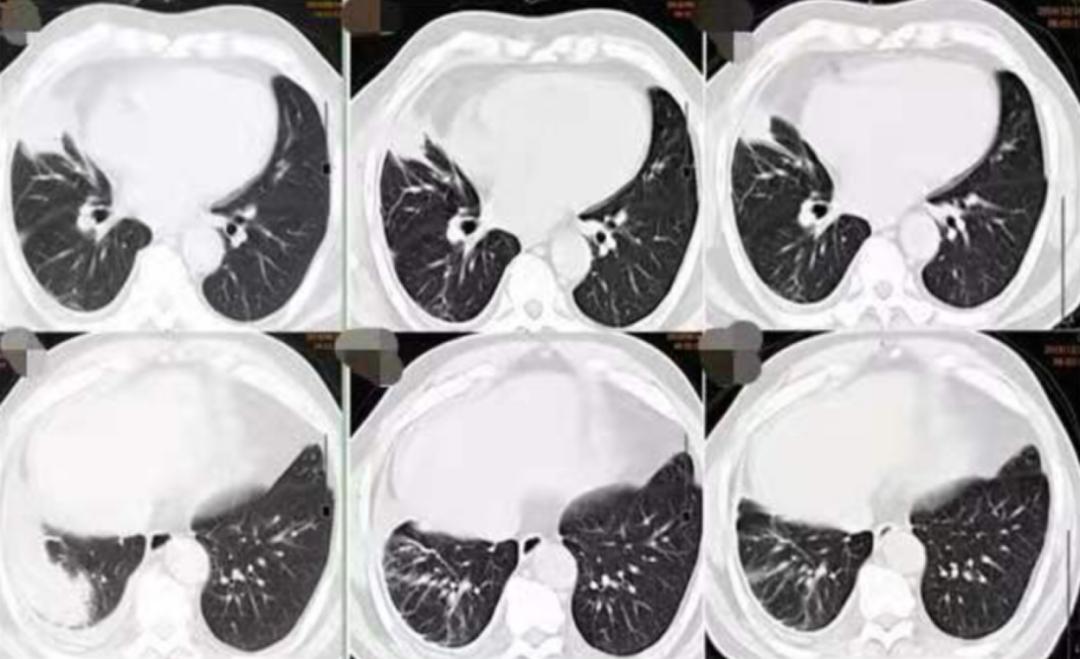

我们给出的治疗方案: (1)抗感染:莫西沙星(拜复乐);(2)对症:羧甲司坦、乙酰半胱氨酸;(3)密切随诊(图14)。

(从左至右)初诊、1月后、4月后:

图14:2019-09-16胸部CT(1月后):右肺中下叶团块、索条灶,右侧胸腔积液,较2019-08-14老片病灶略吸收,积液减少。2019-12-16胸部CT(4月后):右肺中下叶团块、索条灶,右侧胸腔积液,较2019-09-16老片病灶略吸收,积液减少。